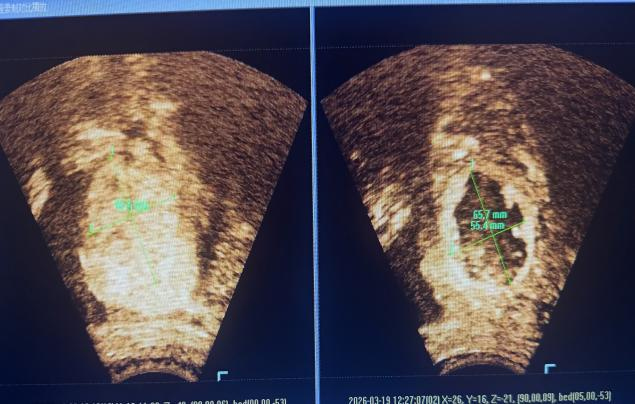

3月19日,治疗如期进行。治疗总时间为3小时,超声消融时间1480秒,功率400W。术后造影显示,病灶区域出现明显无灌注区,肌瘤消融率达85%。术中患者生命体征平稳,仅偶有治疗区轻微疼痛,腹壁及治疗区皮肤完好无损。术后患者即可下床活动,2小时后恢复正常饮食,次日顺利出院。